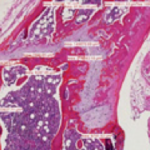

Histomorphometric, or digital image, analysis is an important tool in the assessment of many types of histopathology changes. Digital photomicrographs are made and imported into image analysis software. The images are analyzed by the software and appropriate calculations and statistical analysis performed. The following are but a few examples of tissues and tissue disorders in which histomorphometry assessments may be informative:

We offer morphometry or digital image analysis in a GLP or non-GLP environment. Our Olympus program is a powerful and useful tool for morphometric assessment. Digital images may be saved and analyzed in a variety of formats and measurements calibrated appropriately.